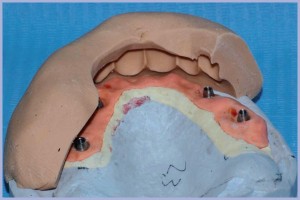

Si sviluppa il modello con gli analoghi moncone e si realizza la struttura metallica di sostegno nella quale si inglobano le cappette in titanio con un cemento “metallo su metallo” (Figg. 5-8).

- Fig. 5 – Modello con mascherina

- Fig. 6 – Modello con cappette in titanio

- Fig. 7 – Modellazione dell’armatura

- Fig. 8 – Modello con cappette in titanio e armatura